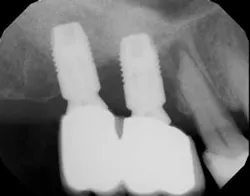

There have been numerous case reports in the literature demonstrating infections of dental implants caused by pathology from the adjacent natural tooth. (1) These infections from adjacent teeth can travel quite quickly to the proximal dental implant (figures 1a and 1b) and cause a rapid degree of bone loss. Treatment can consist of loss of teeth, loss of the dental implants, and/or costly regenerative repair (figure 2). (2) This situation is highly preventable if detected early and endodontic therapy is initiated.